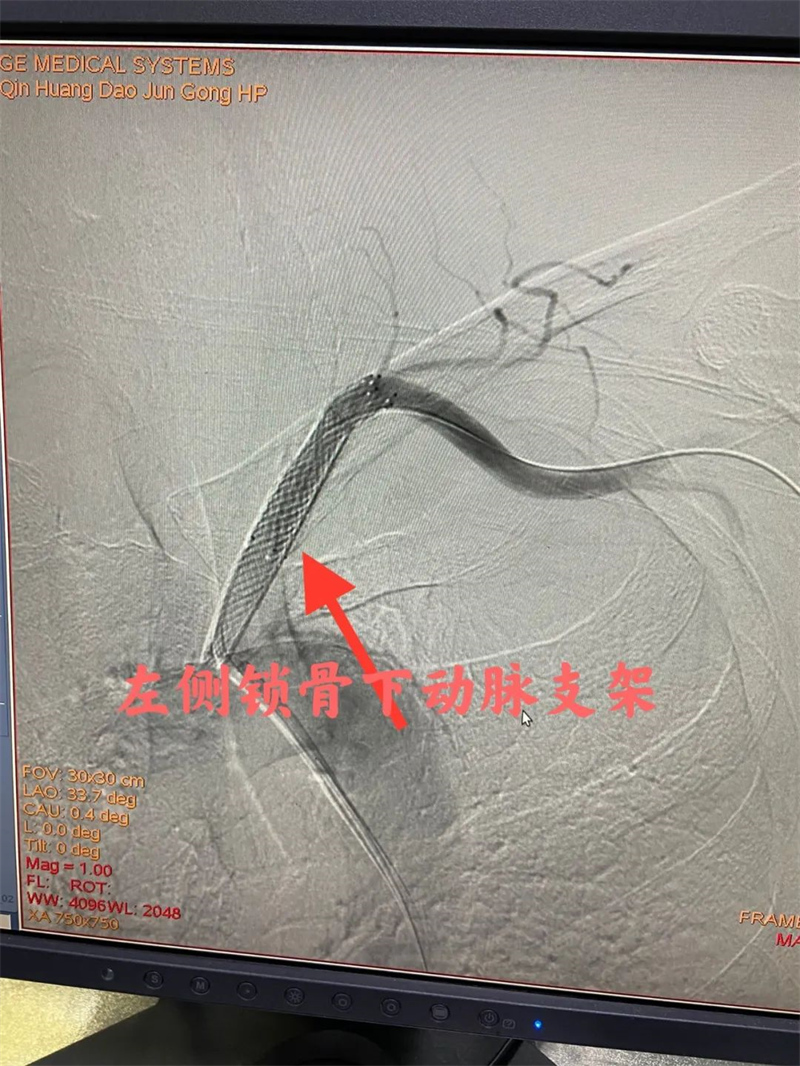

经过充分的准备后,心血管内二科及神经血管介入科团队通过股动脉穿刺,为患者顺利完成冠状动脉造影、肾动脉造影及左侧锁骨下动脉造影。冠状动脉造影结果提示患者前降支远段70%狭窄,确诊为冠状动脉粥样硬化性心脏病。肾动脉造影提示左侧肾动脉起始段中度狭窄,明确了肾动脉狭窄。左侧锁骨下动脉造影提示起始段次全闭塞。成功植入两枚支架,术后患者头晕缓解,左侧桡动脉搏动有力。